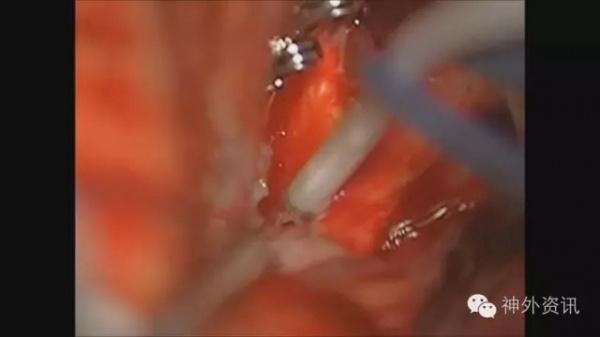

经终板三脑室切开引流置管术(见图4、图5、图6、图7).

图4. 经终板三脑室切开引流置管术。

图5. 经终板三脑室切开引流置管术。

图6. 经终板三脑室切开引流置管术。

图7. 经终板三脑室切开引流置管术。

经额下终板入路是颅咽管瘤的常用入路;而在动脉瘤手术中,亦可以通过打开终板,进一步的释放脑脊液降低颅内压,以达到Slack Brain,减少额颞叶的牵拉。有学者提出,破裂动脉瘤术中打开终板,不仅可有效降低颅压,还可降低术后交通性脑积水的发生率,但此观点在某些单中心回顾性研究中并未得到证实。

对于H&H分级、Fisher分级较高的SAH病例,术中留置脑室引流管有利于术后的脑压下降及脑压监测,血性脑脊液的持续引流有利于减少血管痉挛及交通性脑积水的发生。

相比于常规Paine’s点穿刺侧脑室留置脑室引流管,经终板留置三脑室引流管优势劣势均十分明显。

优点没有额外的脑实质损伤;

不会出现穿刺道血肿;

操作均在显微镜下直视进行,无穿刺失败率。

引流管较脑室引流管细,容易出现引流管堵塞;

对于指向下的前交通动脉瘤,打开终板时容易导致动脉瘤破裂;

“Red,Angry,Swollen Brain”,此种脑压非常高的情况,仅通过释放颅底池脑脊液,很难暴露终板,此种情况仍需行Paine’s点穿刺。